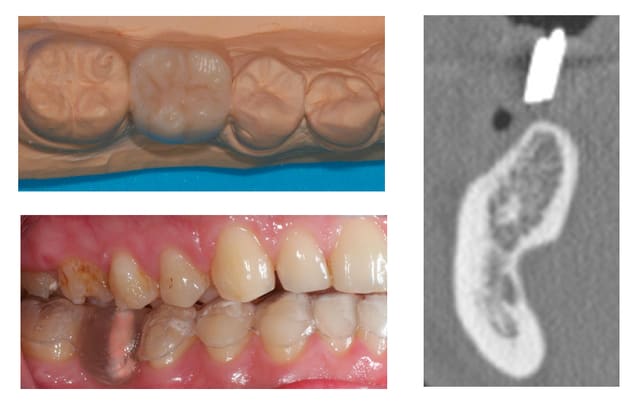

Bon je m'y colle, c'est pas le même niveau qu'olivier, mais ce sujet étant censé être pour les débutants je poste.

Patient 26 ans, à qui il manque 46, 25 et 26.

Pour l'instant je vous propose la partie préparation et mise en place de l'implant en 46, la suite peut être bientôt.

Dans l'ordre si le site veut bien, wax-up ( cirage pour céramik ;) ) , guide radio, et scan.

Photos pré-op, indicateur de direction en place et post-op.

Il s'agit d'un implant astra osseospeed de 5 mm de diamètre et 9 de long.

Prothèse prévue à 6 semaines.

puisque tu veux de la critique, impec (juste que je l'aurais mis à peine, mais vraiment à peine moins infra-osseux)

c'est à cause du profil de la crête, en fait l'implant est juxta-osseux en vestibulaire, par contre moi je le trouve ( légèrement ) trop distal.

bonne iconographie et bon travail, même si légèrement distal.

les critiques (dans le sens positif bien sur):

félicite le proth beau wax up.

j'aurais fait une petite expansion en bas ( tu t'en doute) pour retrouver un bombé vestibulaire et

j'aurais mis un peu plus long (12?)

pour le haut je me laisserais aller à une distraction (c'est vraiment un beau cas pour commencer) plutôt qu'une rog, mais tu as fait ton choix.